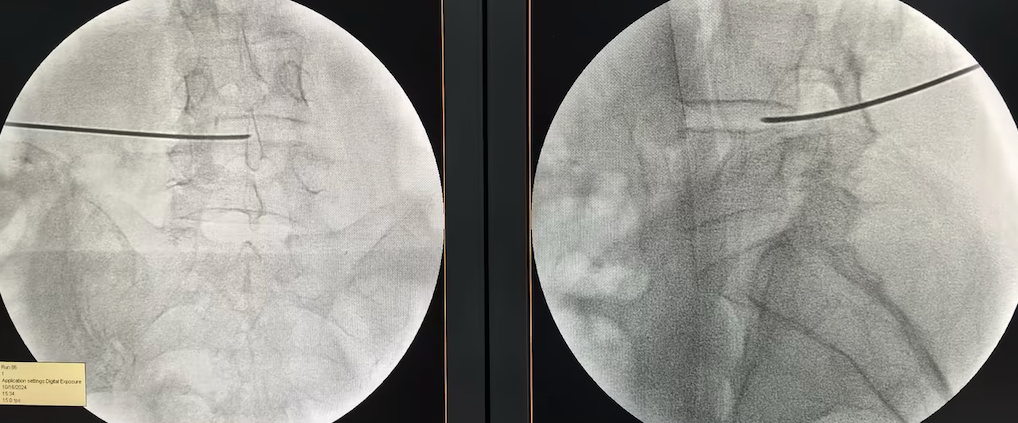

△胸椎爆裂骨折复位内固定技术

小杨母亲的朋友此前在青岛医院顺利完成了颈椎和腰椎手术,将青岛医院推荐给了小杨。出于对医院和朋友的信任,一家人连夜购买机票,跨越580公里奔赴青岛。“最好手术,长期拖着可能造成永久性驼背和慢性腰背疼痛,甚至造成脊髓损害。”李强主任说。

完善检查后,脊柱外科团队为患者实施了胸椎骨折切开复位内固定术,仅用7公分切口就完成了高难度复位固定。术后第三天,小杨已能戴着护具下床活动,目前已顺利出院。